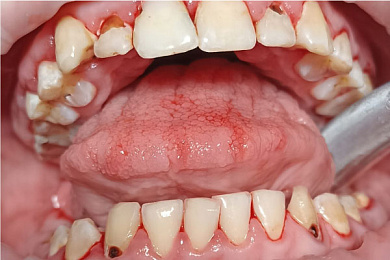

Показаниями считаются следующие симптомы::

- Повышенное количество зубного налета

- Отложения зубного камня

- Процессы воспаления дёсен

- Регулярная профилактика заболеваний полости рта